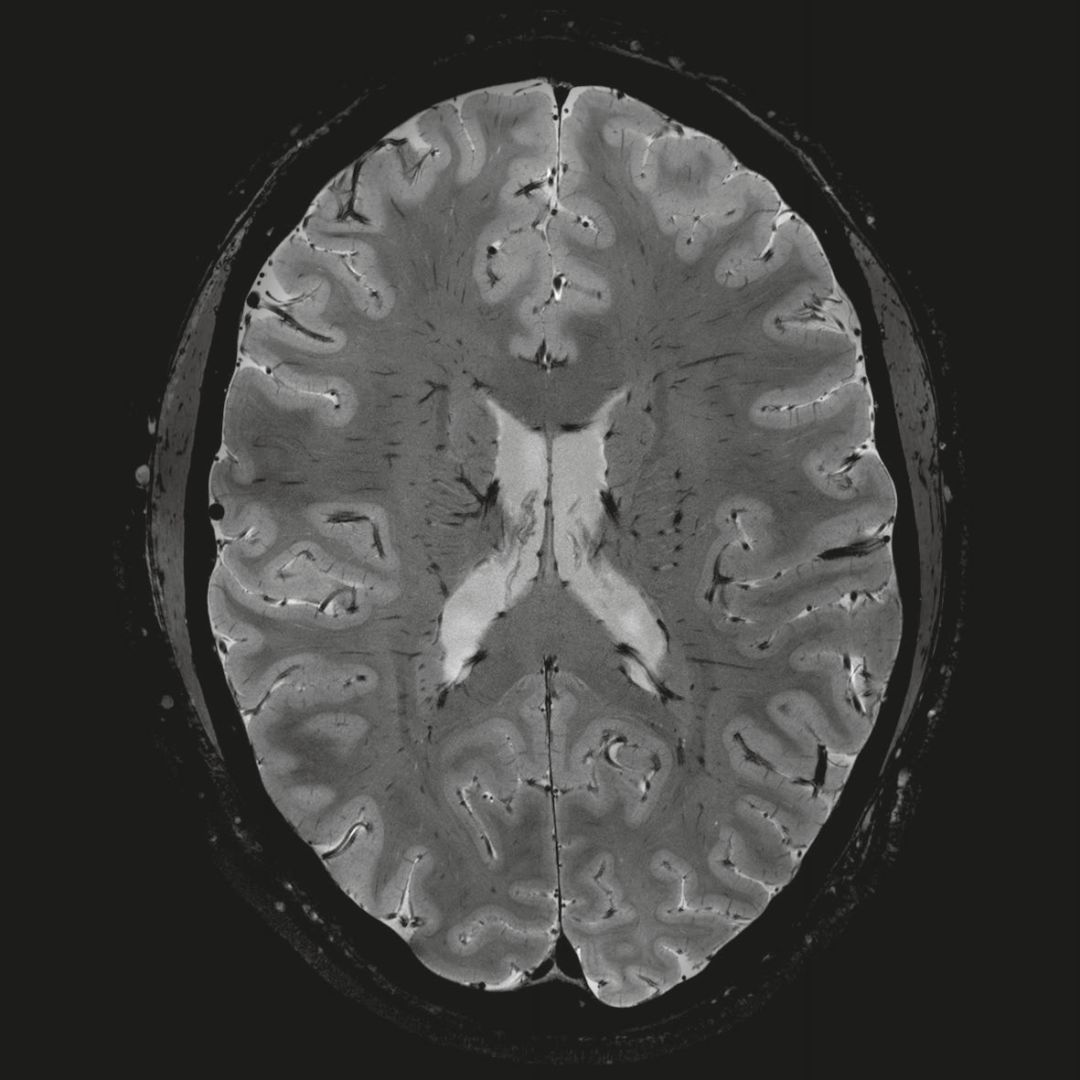

但近年來,西門子與科研機(jī)構(gòu)共同研究發(fā)現(xiàn),7T提供了數(shù)倍于傳統(tǒng)3T磁共振的信噪比和空間分辨率,在神經(jīng)、血管、腫瘤、骨關(guān)節(jié)等多個方面都會帶來全新的突破性進(jìn)展。尤其是在目前常規(guī)影像設(shè)備難以診斷的神經(jīng)退行性疾病如阿茲海默氏病、帕金森病等疾病的發(fā)病機(jī)理、早期診斷、治療方案確定以及治療效果評估上,有著極大的潛力。

MAGNETOM Terra在業(yè)界首次實(shí)現(xiàn)了兩倍于傳統(tǒng)7T的超強(qiáng)梯度性能,實(shí)現(xiàn)超快速、超高效、超高分辨功能磁共振成像。如此高性能的梯度系統(tǒng)無論對于科研還是臨床都帶來了更多可能。

1毫米的各向同性分辨率DTI:神經(jīng)纖維束的交叉細(xì)節(jié)顯示

0.8毫米的各向同性分辨率:精確劃分灰質(zhì)和白質(zhì)

0.8毫米的各向同性分辨率:超精細(xì)的解剖細(xì)節(jié),例:小腦的精細(xì)結(jié)構(gòu)

超精細(xì)的解剖細(xì)節(jié):T2對比

0.17 x 0.17 x 0.8毫米分辨率超高。

(TOF)300微米的各向同性分辨率顯示最小的血管